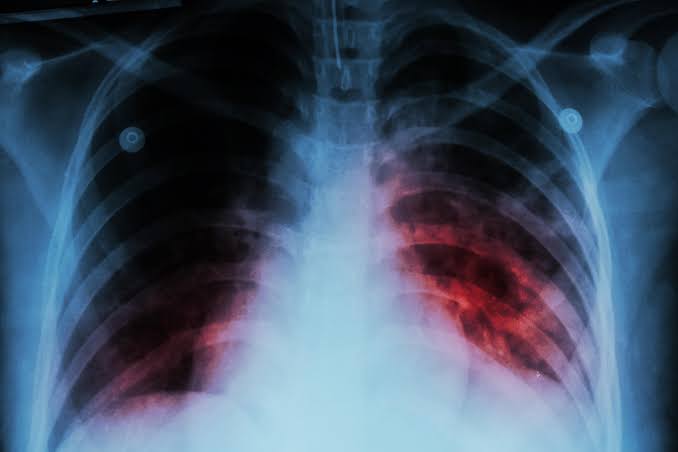

Tuberculosis: Enfermedad bajo vigilancia epidemiológica

El secretario de salud explicó que la tuberculosis puede afectar a cualquier persona y a cualquier edad. Debido a su impacto en la salud pública, es una enfermedad bajo vigilancia epidemiológica y requiere un control obligatorio del tratamiento.

La tuberculosis es una enfermedad infecciosa que se transmite por el aire, principalmente cuando una persona infectada tose o estornuda.